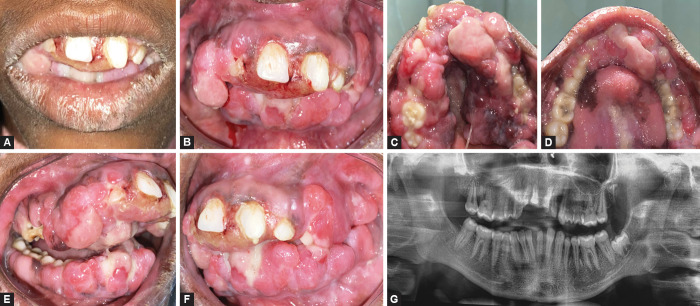

Case description: A 15-year-old girl presented with a generalized, severe, disfiguring PGE involving the entire maxillary and mandibular arch, causing an impairment of oral hygiene, mastication, speech, and esthetics. Clinical indices and oral health impact profile-14 were recorded at baseline, 1, 6, 9, 12, and 18 months. Phenytoin was replaced by the drugs levetiracetam and oxycarbamazepine. NSPT was initiated, which included plaque control measures and oral prophylaxis. There was a consistent improvement in OHRQoL scores from baseline (score 52 out of 56) to 6 months (score 15; 70% improvement) and a decrease of subscale scores (score 8-2) for psychological discomfort, psychological disability, and social disability, following drug substitution and NSPT. Thereafter, the relatively smaller, nonresponsive, persistent growth was treated with gingivectomy. Complete restoration of gingival health and no signs of recurrence were seen at 18 months (score 0).